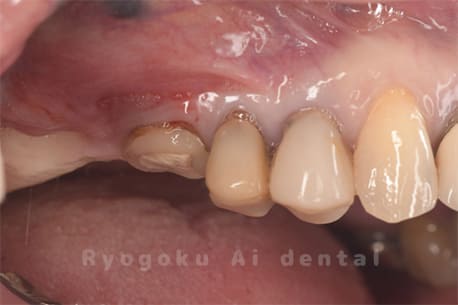

Case14

-

- 抜歯原因

- 重度カリエス

- 治療内容

- クラウンレングスニング治療

- 治療費用

- 44,000円

他院で抜歯と言われた、とのことでご来院された患者さまです。クラウンレングスニングを行い、保存致しました。大変満足して頂けました。

<リスク・副作用>

治療後、痛みや違和感、出血、腫れなどが出る事があります。喫煙者、糖尿病などの方の場合、歯が生着しない場合があります。